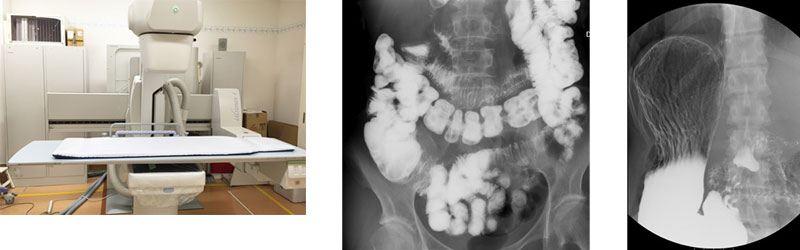

透視検査とは

透視検査とは、食道・胃・大腸などの消化管の検査や整形外科系の骨折・脱臼等の整復術、脊髄・関節腔の造影、さらには各臓器の機能や形態を調べたり、手術後の狭窄や漏れの状態の確認をおこないます。

当院の透視検査

透視検査は多岐に渡っており、当院では豊富な実績とその技術が高く評価されている内視鏡治療との組み合わせで、EST(内視鏡的乳頭切開術)、ERCP(内視鏡的逆行性胆管膵管造影)、ERBD(内視鏡的胆管ドレナージ)等の治療もおこなっています。

また、当院のX線透視撮影装置はFPD(フラット・パネル・ディテクタ)方式を用いているため、従来のX線透視撮影装置と比べ、少ない被ばく線量で画像にゆがみがなく広い範囲を観察することができます。